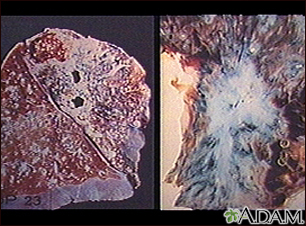

Tuberculosis in the lungBackTuberculosis in the lungTuberculosis is caused by a group of organisms: Mycobacterium tuberculosis, M bovis, M africanum and a few other rarer subtypes. Tuberculosis usually appears as a lung (pulmonary) infection. However, it may infect other organs in the body. Recently, antibiotic-resistant strains of tuberculosis have appeared. With increasing numbers of immunocompromised individuals with AIDS, and homeless people without medical care, tuberculosis is seen more frequently today. (Image courtesy of the Centers for Disease Control and Prevention.) E-mail FormEmail ResultsName:Email address:Recipients Name:Recipients address:Message: